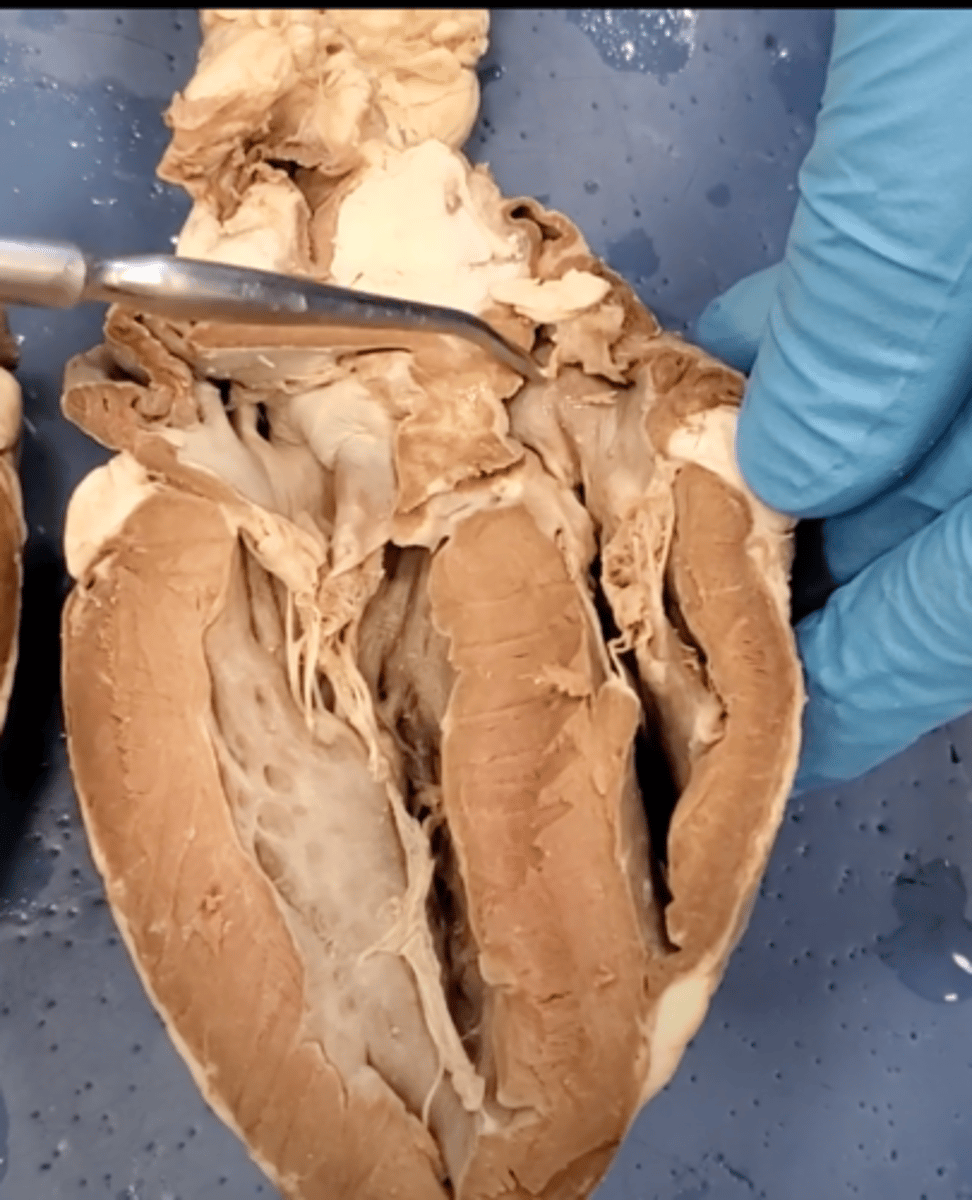

Tricuspid Valve (Right Atrioventricular Valve)

1-valve

Bicuspid valve (Left Atrioventricular Valve)

2-valve

Pulmonary Semilunar Valve

3-valve

Aortic Semilunar Valve

4-valve

Right Atrium

1-chamber

Left Atrium

2-chamber

Right Ventricle

3-chamber

Left Ventricle

4-chamber

Inferior Vena Cava

5-A vein that is the largest vein in the human body and returns blood to the right atrium of the heart from bodily parts below the diaphragm.

Superior Vena Cava

6-A vein that is the second largest vein in the human body and returns blood to the right atrium of the heart from the upper half of the body.

Aorta

7-The large arterial trunk that carries blood from the heart to be distributed by branch arteries through the body.

Pulmonary Trunk

8-carries blood from right ventricle to pulmonary arteries

Pulmonary veins

9-a vein carrying oxygenated blood from the lungs to the left atrium of the heart.

yellow sash of fat that tells you this if the front side of the heart (dissection)

pulmonary trunk (dissection)

t-shaped ribbon of fat on back side of heart (dissection)

left auricle (dissection)

right auricle (dissection)

left ventricle (dissection)

right ventricle (dissection)

right atrium (dissection)

left atrium (dissection)

bicuspid valve (dissection)

tricuspid valve (dissection)

aortic semilunar valve (dissection)

located between the left ventricle and the aorta

chordae tendineae (dissection)

thin bands of fibrous tissue that attach to the valves in the heart and prevent them from inverting